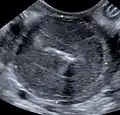

Größere solide Tumoren können unter Umständen bereits durch die Bauchwand ertastet werden. Weitere Hinweise können eine Sonografie, eine Endoskopie oder eine Bauchhöhleneröffnung geben. Die Diagnose wird wiederum durch Biopsie und Zytologie gestellt.

-

Von einem Lymphom infiltrierte Darmwand. Die Muskularis stellt sich verdickt dar. Die Abgrenzung zur IBD kann schwierig sein. -

Von einem Lymphom veränderter Dünndarm. Der rote Pfeil markiert eine unveränderte Darmwand mit normaler 5-Schichtung. Der gelbe Pfeil markiert das veränderte Gewebe mit Umfangsvermehrung, teilweisem Verlust des normalen Wandaufbaus und verminderter Echogenität. -

Von einem Lymphom infiltrierte und verdickte Magenwand. Im Bereich der hypoechogenen Struktur kam es zur Auflösung des physiologischen Wandaufbaus, der links distal davon noch andeutungsweise erkennbar ist. -

Vollständig von einem Lymphom infiltrierte Darmwand. Die normale Schichtung ist vollständig verschwunden. -

Lymphom im terminalen Ileum, das pathohistologisch als high-grade Lymphom klassifiziert wurde.